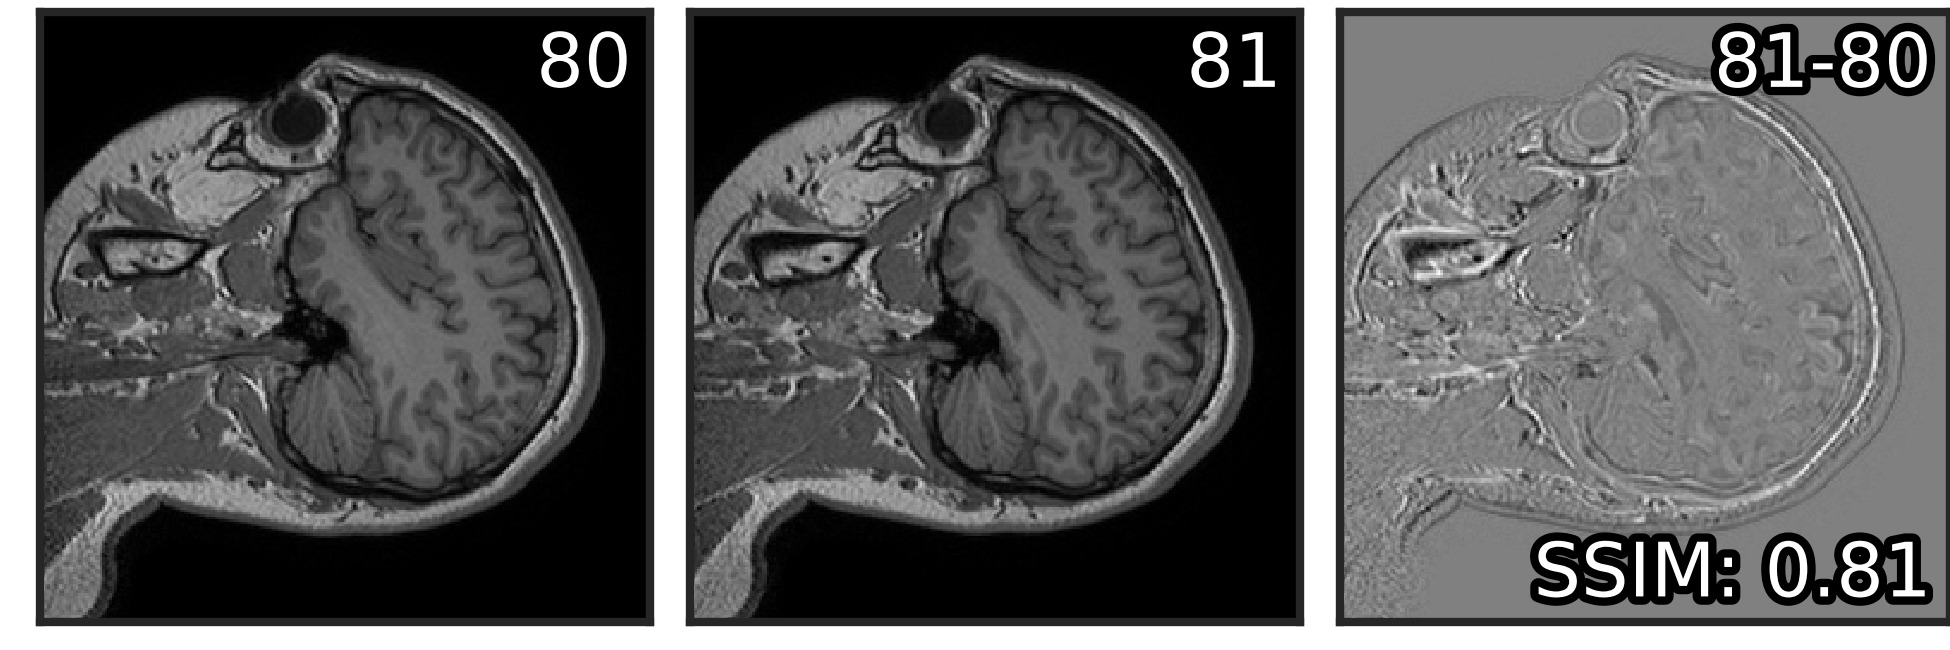

Adding four neighbors to the Noise2Noise input increased PSNR by dB both before and after post-processing (Table 1). Overall, limiting the number of neighbouring planes to four (two from each side) proved optimal, resulting in the greatest performance benefits with reasonable computational costs in both modes (Figure 4). Using a single image stack for training in a self-supervised mode with four neighbours in the input, we outperform the original Noise2Noise model by dB.

Visually, the level of detail in MRI denoised with Noise2Stack in copy-supervised mode has noticeably increased comparing to Noise2Noise, as can be seen in Figure 3 (additional illustrations provided in Supplementary material, Figure S1). Brain gyri in the reconstructed images are clean and sharp even for the cerebellum where they are tiny. In self-supervised mode Noise2Stack results are expectedly less detailed and match Noise2Noise by sight. However, this mode demands twice less data, being able to learn from a single copy. For the fluorescent microscopy, Noise2Stack in self-supervised mode did not outperform supervised Noise2Clean, but has shown comparable results.